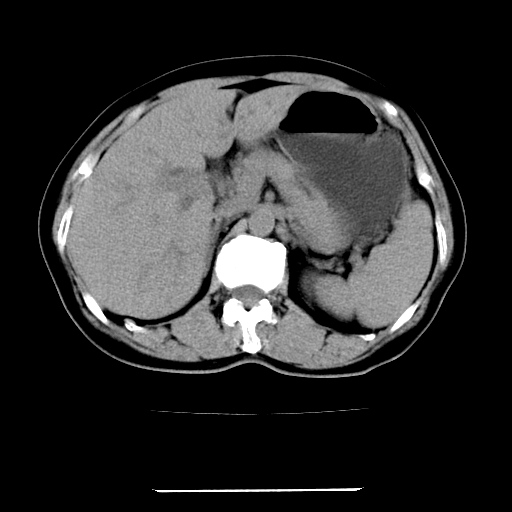

标题: CT22301:女,67岁,上腹部疼痛一周伴皮肤黄染,无发热。 [打印本页]

女,67岁,上腹部疼痛一周伴皮肤黄染,无发热。

左叶肝内胆管结石,并远端肝内胆管扩张。

考虑:肝内胆管结石继发肝内胆管扩张,右肾旋转不良。

肝内外胆管结石并肝内胆管扩张。

建议薄层观察,除外肝门部胆管细胞癌

考虑肝胆管癌;胰头占位?【形态失常,体积增大】

1、肝门高密度影下层面和胰头层面可见轻度胆管扩张,而静脉和延迟期均未见扫描完胰头,不能完全排除胰头占位。2、肝门部高密度影,考虑钙化或结石。

考虑肝门胆管癌伴门脉左支受侵包埋,建议mrcp进一步检查。